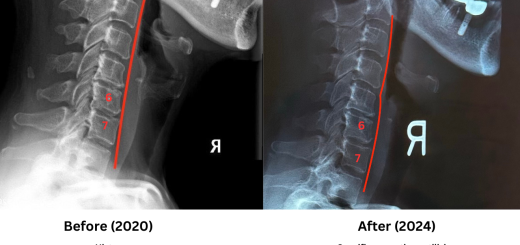

Preservation of Spinal Disc Health

• Pre and Post X Rays